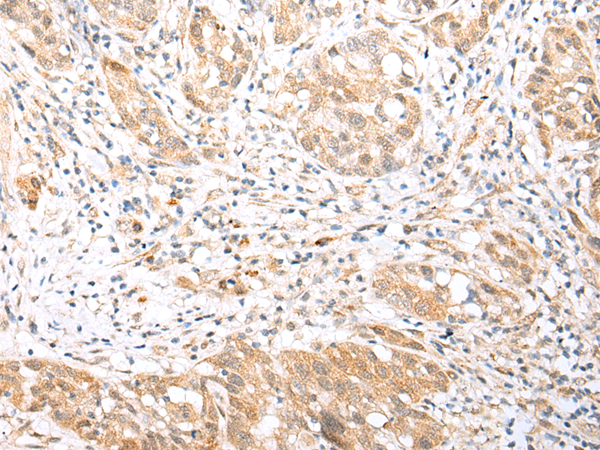

IHC positive control: |

Human thyroid cancer and human gastric cancer |

IHC Recommend dilution: |

25-100 |